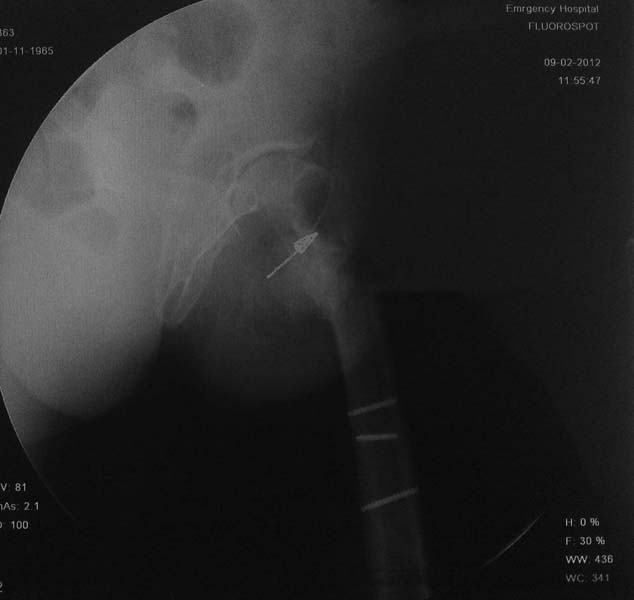

Рентгенограмма пациента А 49 лет с диагнозом: Неправильно консолидированный подвертельный перелом левой бедренной кости, с варусной деформацией.

На рентгенограммах левого тазобедренного  сустава шеечно-диафизарный угол 90 градус. Признаки артроза 2 ст и очаг остеосклероза  в проекции ШДУ (указан стрелкой).

Имя     : lat.jpg